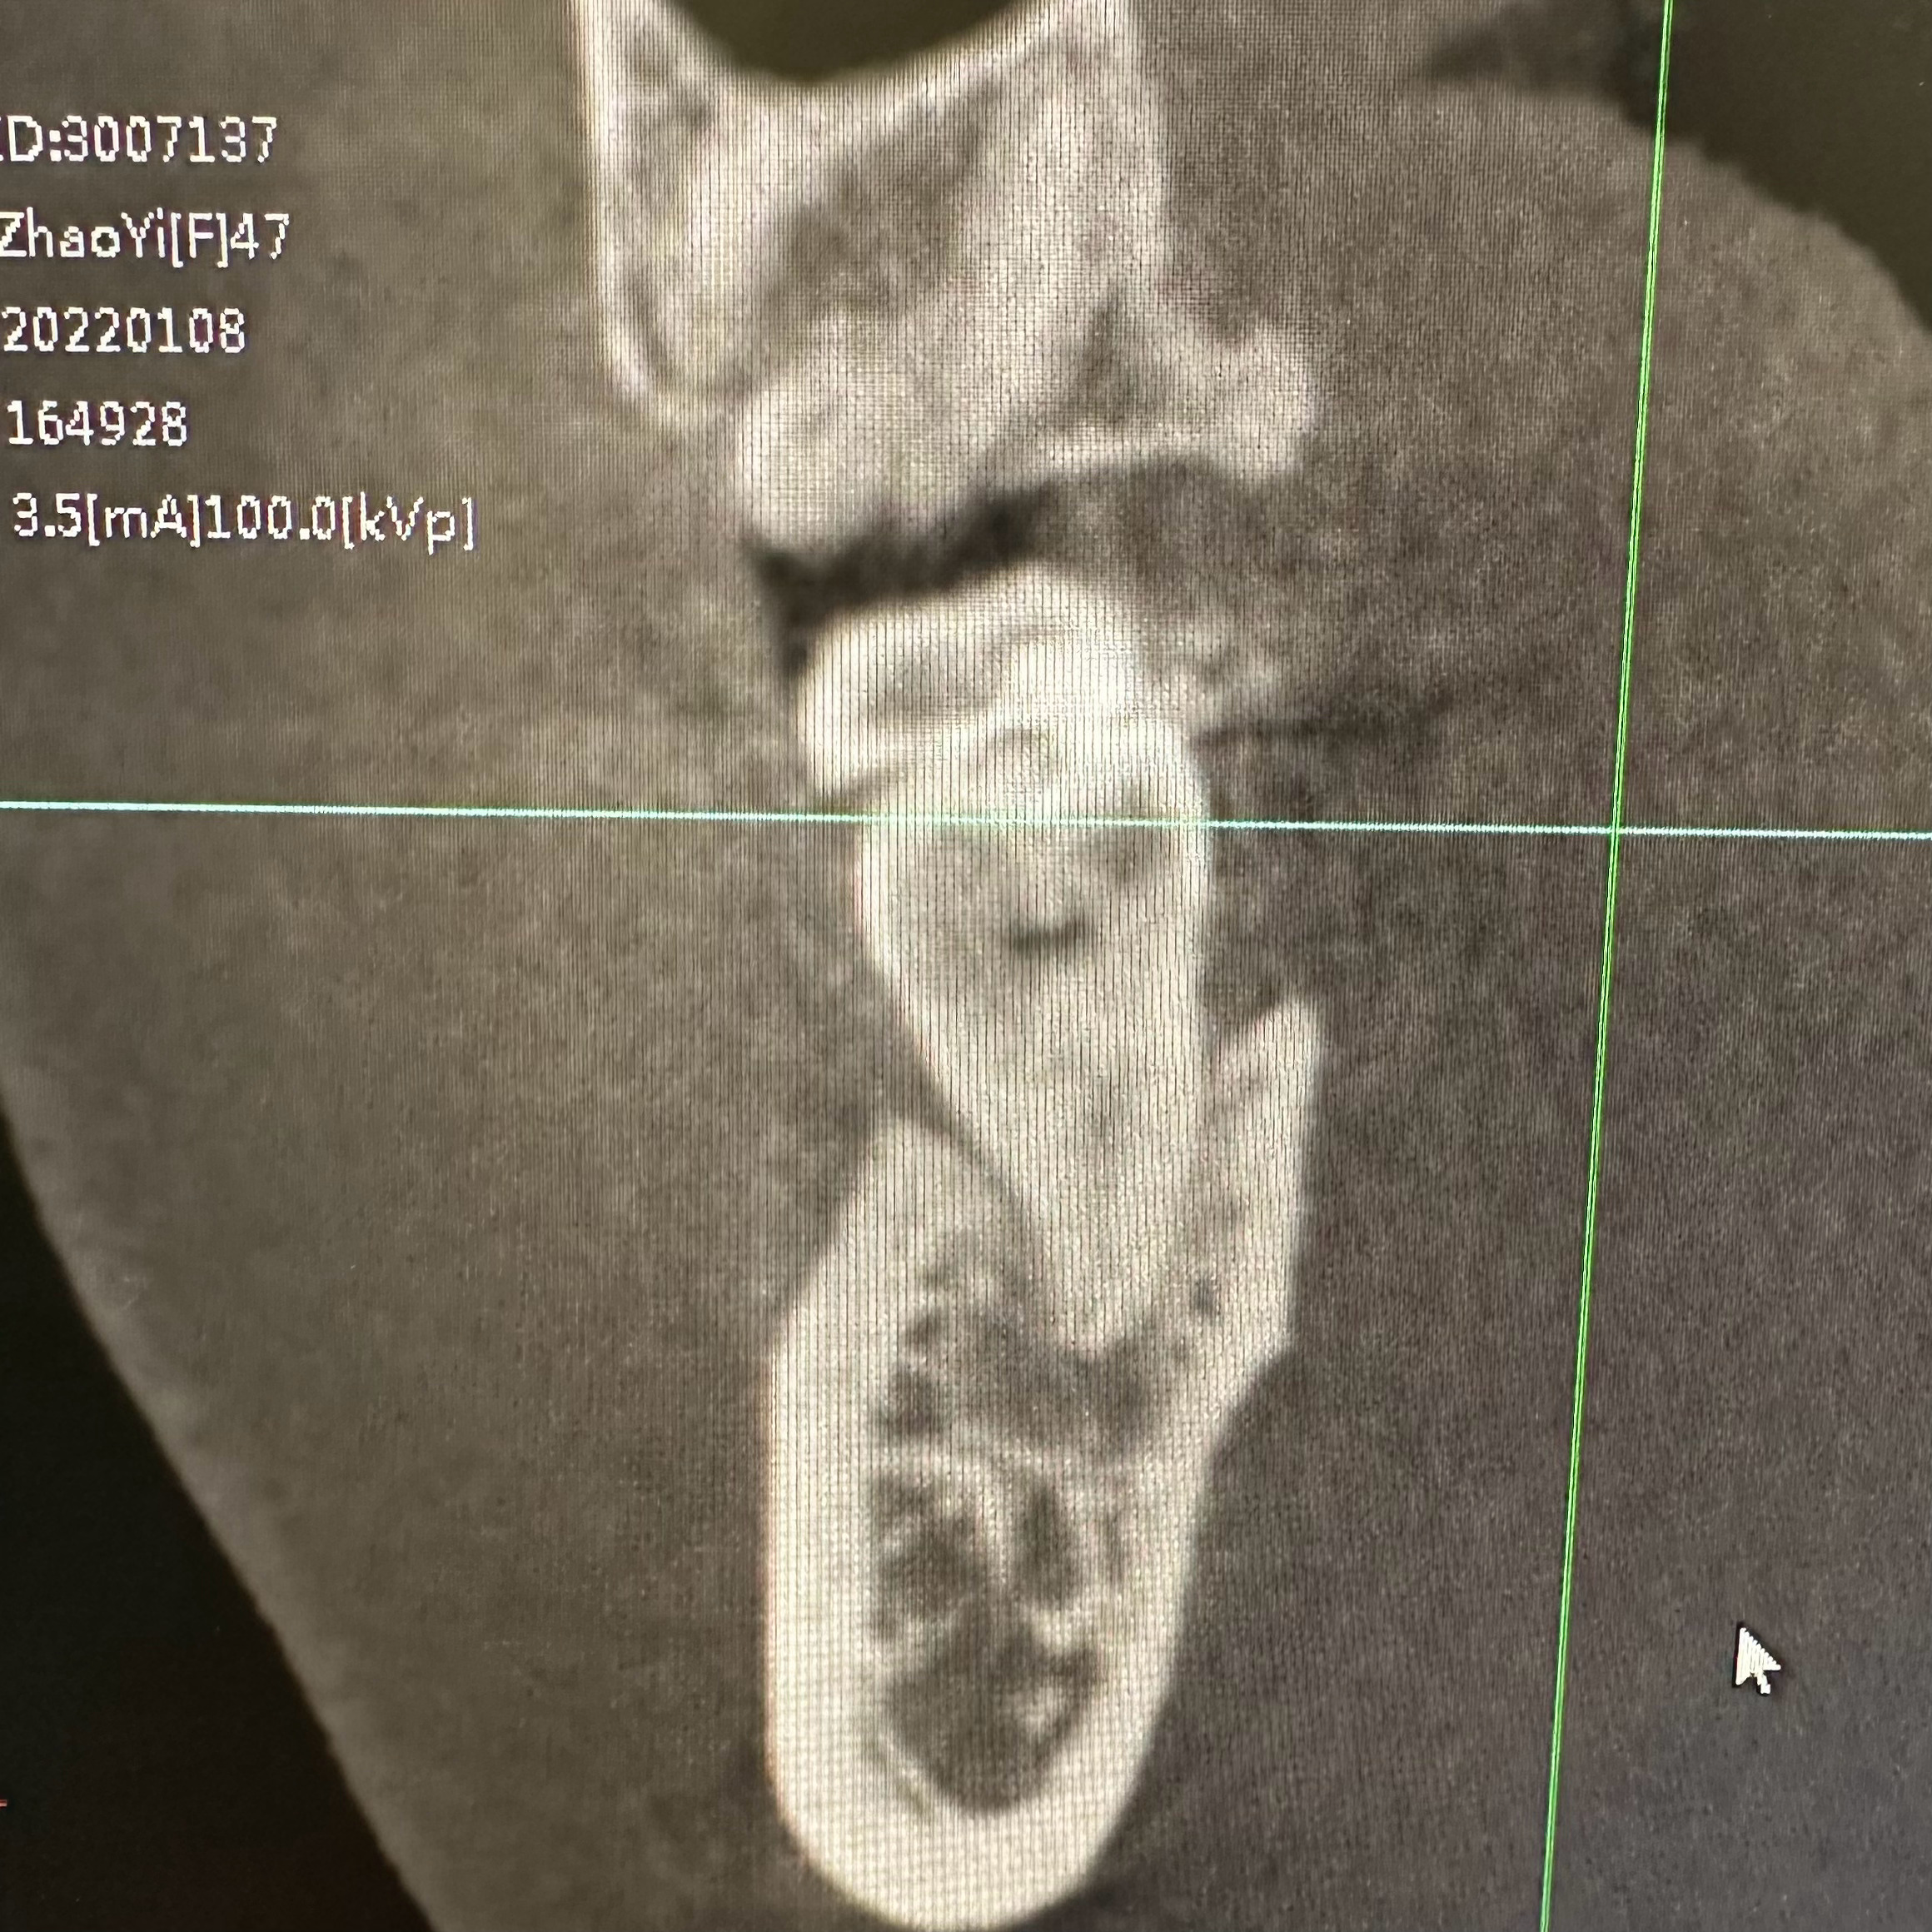

图一:

被挤破并累及到神经,

情况变复杂,

需要处理神经之后做烤瓷牙。

一个月都处理不完,

还得去三四次。

图四:

还有一颗横着长的智齿,

也可能挤到旁边牙的压根,

要不要手术取出,

还没跟林医生商量,

处理完被挤出洞的那颗牙之后再说吧。